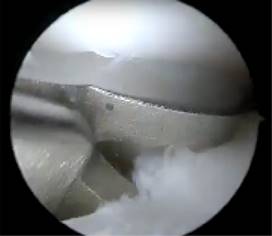

Durante la artroscopía de la rodilla derecha, se encontró una lesión compleja en el menisco medial, que fue diagnosticada como un menisco discoide. Además, se observó una abundante sinovitis y Hoffitis, así como la presencia de una banda fibrosa en la parte ventromedial (Figuras 3 y 4). Se realizó una plastía del menisco medial mediante saucerización y se determinó que el menisco medial estaba estable, por lo que no se requirió el uso de suturas meniscales (Figuras 5 a 7). También se realizó la resección de la banda fibrosa, sinovectomía y Hoffectomía.

Figura 5: Visión artroscópica de la revisión de la estabilidad del cuerpo del menisco medial con gancho palpador.